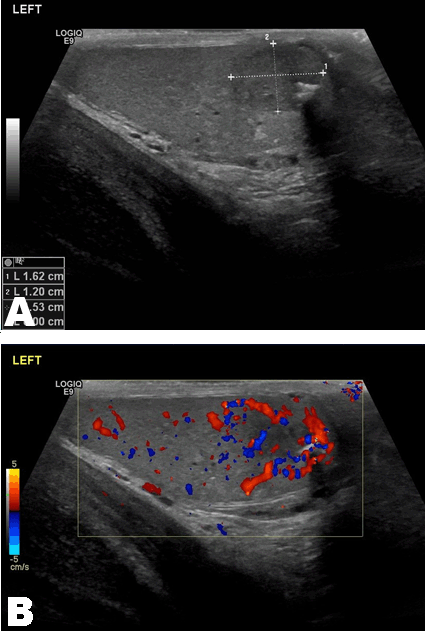

A 28-year-old male presented via the fast-track cancer pathway to urology clinic with a preceding history of a new onset left sided testicular pain and swelling. His general physician initially prescribed antibiotics for suspected epididymitis, but there was poor response over the ensuing weeks. An ultrasound scan was also requested and performed shortly after his first presentation (Figure 1). However, the report was not reviewed until the point when he was referred to urology two months later. This initial ultrasound scan reported a well-defined solid lesion in the lower pole of the left testis, measuring 19x12x10 mm with a calcific area and internal vascularity noted (Figure 1). The right testis was normal, as were both epididymis. A right sided varicocele was also noted.

Figure 1: Ultrasound scan left testis, (A) Testicular well-defined solid lesion with calcific area, (B) Internal vascularity of lesion demonstrated.